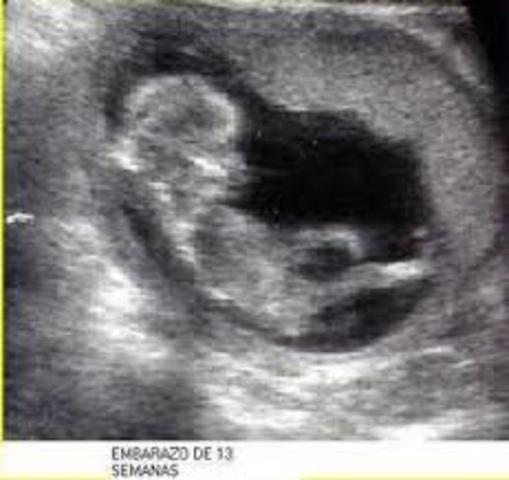

• Semana decimo tercera de gestación

Semana decimo tercera de gestación

¡Felicidades, ya estás en el segundo trimestre de tu embarazo!

El feto mide unos 7 centímetros y pesa alrededor de 14 gramos.

A partir de esta semana, su peso y su longitud aumentarán mucho más rápidamente. Ya ha aprendido a respirar. El cartílago óseo empieza a convertirse en hueso y el cuerpo empieza a crecer más rápido que la cabeza.

Las orejas y los ojos se están moviendo hacia su posición. Ya han aparecido los 27 huesos de la mano y ya ha empezado a experimentar el sentido del tacto. Ya t